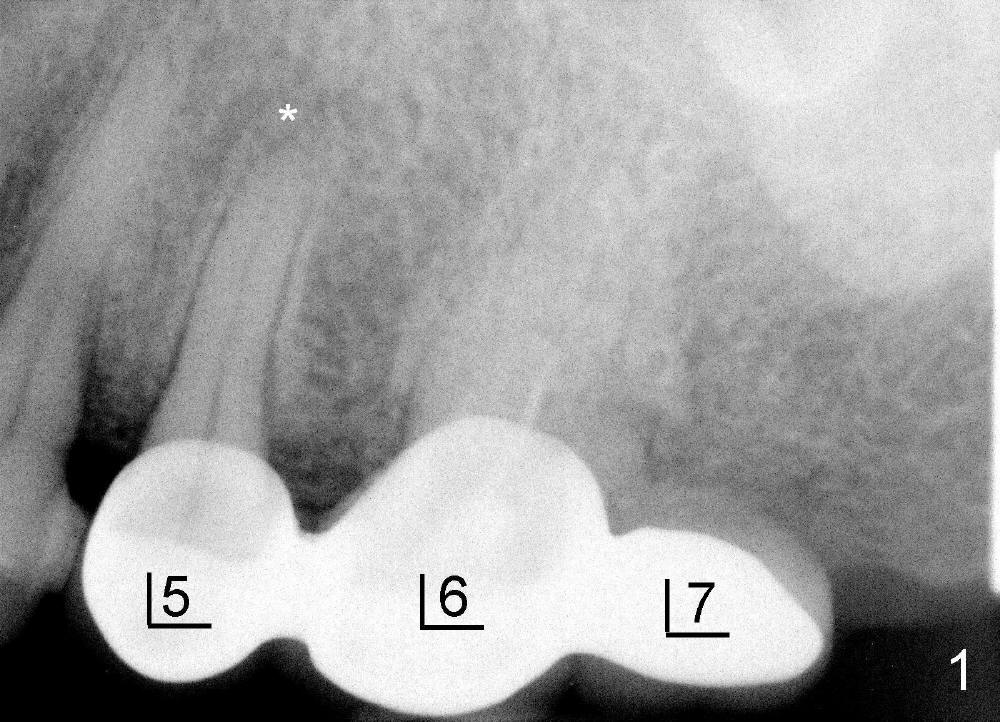

在倪先生五号牙根管治疗中,我们使用外科吸管,Apex locator很容易使用,插入主牙胶尖(图五),顺利完成根管治疗(图六)。